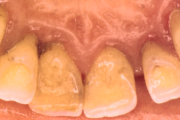

Krooniline parodontiit

Krooniline parodontiit on mikroobide poolt põhjustatud hammaste tugikudede põletik, mille tulemusena tekib progresseeruv alveolaarluu (nähtav röntgenograamil) ja periodontaalligamendi destruktsioon, igemetaskute moodustumine, igeme retsessioon või mõlemad kahjustused kombineeritult. Loe edasi »

- puudulik suuhügieen (5)

- igemepealne hambakivi (5)

- igemealune hambakivi (4)